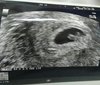

ja natychmiast zadzwoniła bym do ginekologa lepiej na zimne dmuchać

Jeśli masz jak to myślę , że dobrze byłoby to skontrolować i pojechać na izbę lekarz zbada i powie co jest grane niż siedzieć tutaj i się martwić to lepiej pojechać i uspokojic